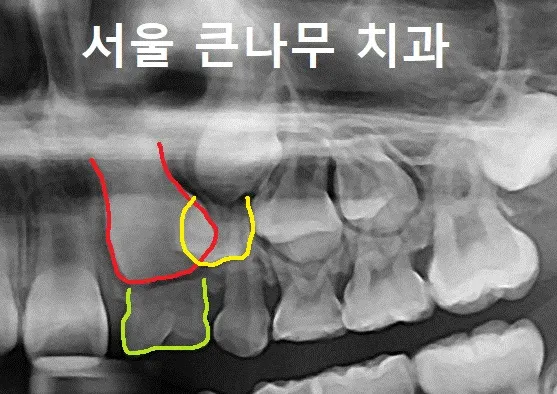

이 환자의 경우, 치과검진과 x-ray를 통해 윗니에 쌍생치가 있다는 것을 알게 되었습니다.

사진을 보시면, 유치 쌍생치가 빠지지 않아 영구치들이 나오지 못한 모습을 찾아볼 수 있습니다. 표시된 쌍생치는 유치이므로 발치를 하고 후속 영구치가 자리 잡을 수 있게 소아교정을 통해 치료 중에 있습니다.